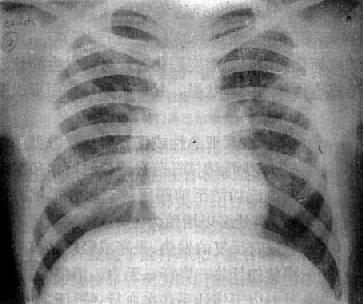

由于病灶系多次血行播散所形成,故X线表现为大小不一、密度不同、分布不均的多种性质的症灶(图3-1-23)。小者如粟粒,大者可为较大的结节状,主要分布于两肺上、中野,下野较少。早期播散的症灶可能已经钙化,而近期播散的病灶仍为增殖性或渗出性。本型结核发展较慢,经治疗新鲜病灶可以吸收,陈旧病灶多以纤维钙化而愈合。恶化时病灶可融合并形成空洞或逐渐转为慢性纤维空洞型肺结核。

图3-1-23 慢性血行播散型肺结核

两肺野布满大小不一、密度不同、分布不均的病灶,

下野较少,膈位置低而平